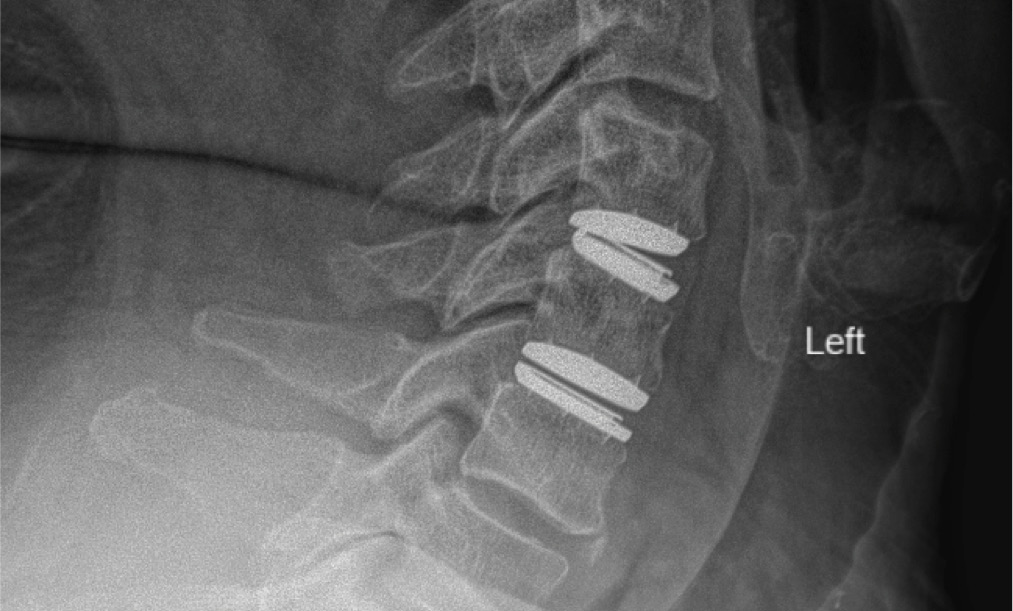

MRIs illustrated mild degenerative disc disease from C4-6 with disc herniations at both C4-5 and C5-6. The axial slice through C4-5 showed a right central disc herniation causing central and mainly right-sided foraminal stenosis. The axial slice through C5-6 showed a central disc herniation also causing central and mainly right-sided foraminal stenosis. The axial slice through C6-7 showed a left-sided disc herniation causing some left-sided foraminal stenosis, however, the patient did not demonstrate any left-sided symptoms.

Upon examination, the patient had good motion on flexion-extension, so fusion was not considered at all. My operative plan was to use prodisc cervical devices and replace both discs at C4-5 and C5-6, giving me the flexibility to use either a domed or flat implant.

During the procedure, prodisc C Vivo fit well within the C4-5 concave endplate. I expected to use a flat endplate prodisc C SK at C5-6, however I trialed the domed prodisc C Vivo and it actually looked good, so I unexpectedly used matching implants.